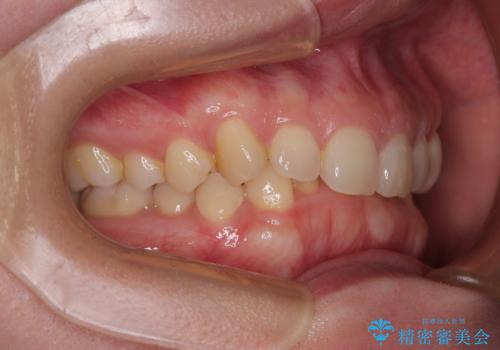

- 下顎前歯が完全に隠れてしまっていることを気にして来院された患者様です。

下顎の臼歯が手前に傾斜していることで咬み合わせが深くなってしまい、下顎前歯が見えないほどに上顎前歯が覆い被さっている状態でした。